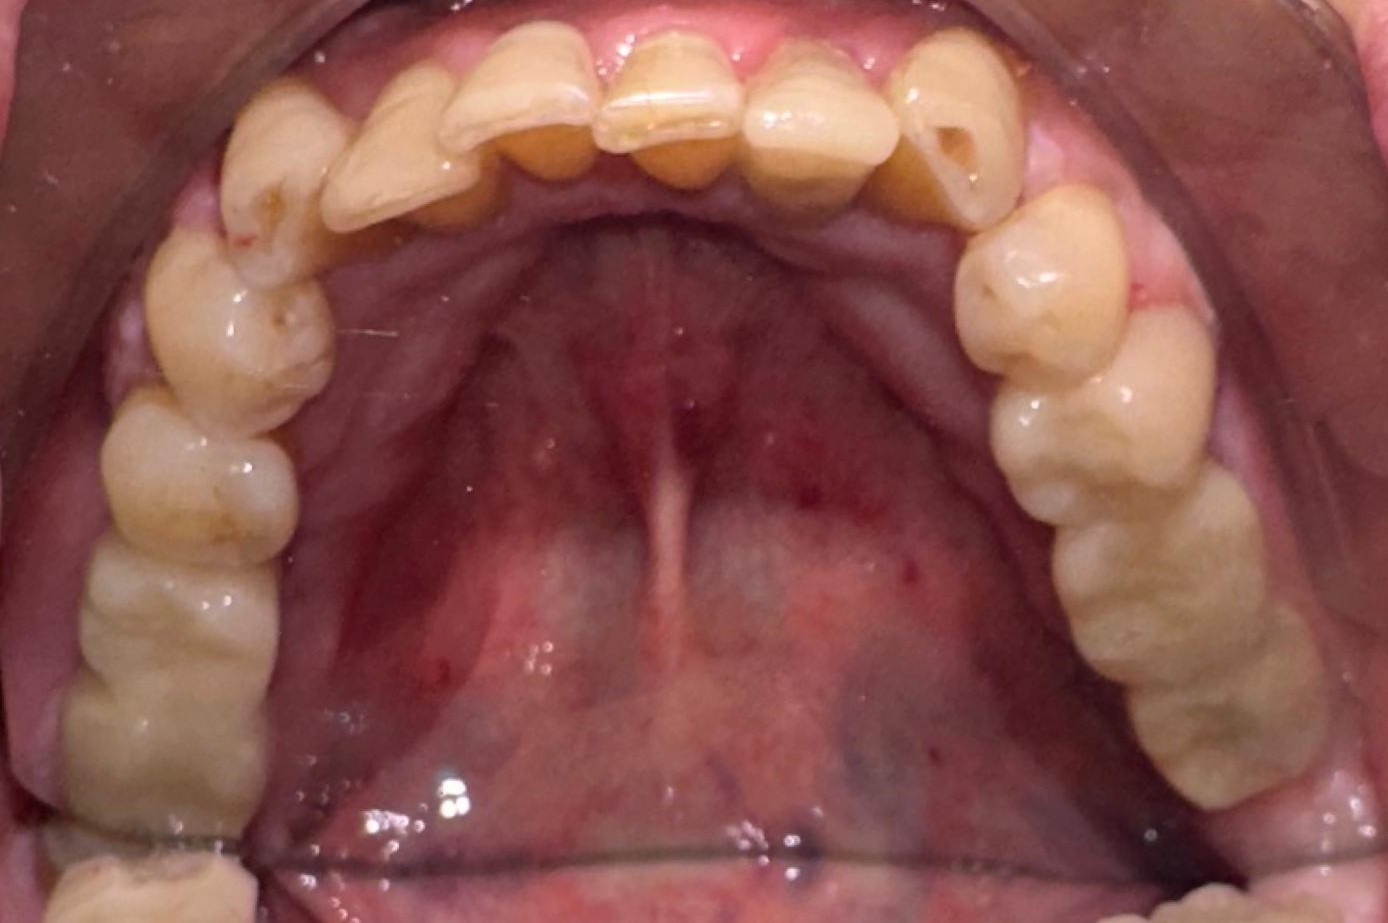

Ya le realicé implantes en el arcada superior hace aproximadamente un año, con mi protocolo de implantes y dientes en el mismo día.

Y en este caso, el paciente iba a quedarse 4 días para pasar el fin de semana y aprovechar para unas mini vacaciones. Le colocamos cuatro implantes en las zonas de molares derecho e izquierdo, más una corona en el sector anterior que tenía una fractura. Y le pude colocar a las 24 horas unas coronas definitivas, sin metal, de manera permanente.